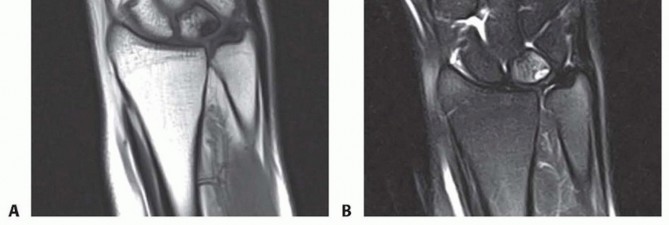

Advanced imaging, specifically Magnetic Resonance Imaging (MRI), is indispensable. We utilize high-resolution 3T MRI, often with intra-articular gadolinium (MR arthrography), to delineate the exact morphology of the TFCC tear and assess the integrity of the intrinsic carpal ligaments.

FIG 3 • B,C. T1 and T2-weighted MRIs of a wrist with ulnar abutment. Note the hyperintense signal on the T2 sequence at the ulnar proximal lunate, indicative of intraosseous edema and microtrabecular trauma secondary to chronic impaction.

The MRI allows us to map the extent of the central perforation. If the tear is small, we know we will need to enlarge it during the débridement phase to gain adequate access to the ulnar dome for the subsequent wafer resection. Furthermore, the MRI helps rule out concomitant pathologies, such as Kienböck's disease or occult carpal fractures, which would drastically alter our surgical algorithm.